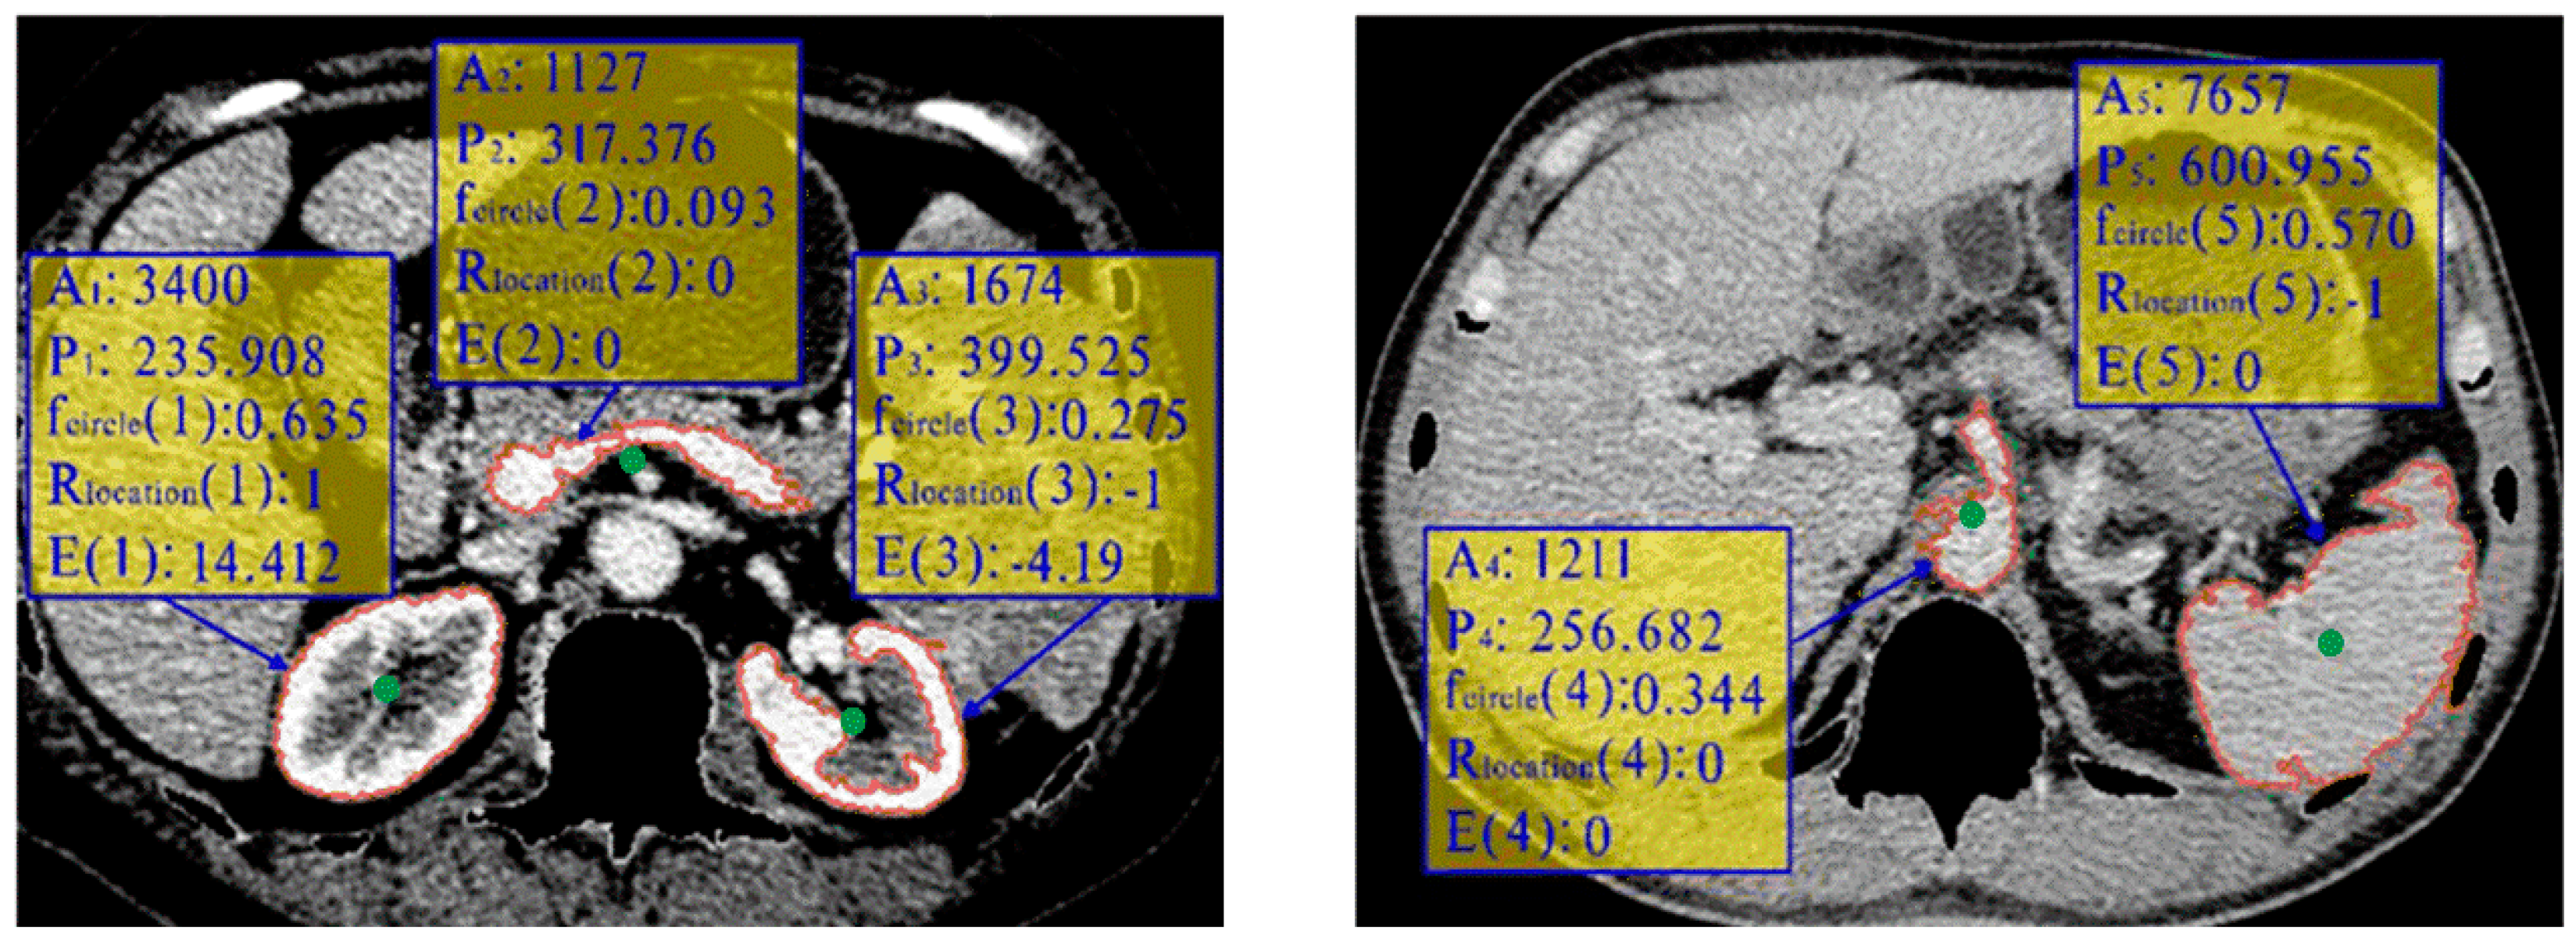

Based on the clustering segmentation results, each slice of the abdominal CT sequence is classified into different classes. While the highest cluster center includes accurately segmented kidney contours, it also contains many interfering contours, such as those of the heart, liver, spleen, abdominal aorta, and inaccurately segmented kidneys. Our goal is to select a large and smooth kidney contour from these candidates. To achieve this, we introduce an automatic selection strategy. Initially, region filling is performed in all connected components of the brightest cluster. Subsequently, to reduce computation time, only the connected regions whose areas range between area min , area max are analyzed. Anatomically, one kidney is located between the spine and liver, while the other is located between the spine and spleen. Additionally, to obtain accurate kidney contours, features based on their area, smoothness, shape, and location are taken into account. The selection formula is expressed as follows:

E ( i ) = A i / P i × R s h a p e ( f c i r c l e ( i ) ) × R l o c a t i o n ( i )

where A i and P i represent the area and the perimeter of the connection component i . The ratio of the area to the perimeter A i / P i provides insights into the component’s size and smoothness, thus filtering out small or non-smooth contours such as the abdominal aorta and improperly segmented kidneys. Kidneys typically have an ellipsoidal shape with smooth edges. Then, R s h a p e f c i r c l e i is defined as follows:

R s h a p e f c i r c l e i = 1 ,     i f   f c i r c l e i > 0.6 0 ,     i f   f c i r c l e i 0.6

where f c i r c l e i = 4 × A i / ( π × L i 2 ) , known as circularity, and L i is the long axis length of region i . Anatomically, one kidney is located between the spine and liver, while the other is located between the spine and spleen. We define R l o c a t i o n ( i ) as follows:

R l o c a t i o n i = 1 ,   i f   c i R l e f t 1 ,   i f   c i R r i g h t 0 ,   o t h e r w i s e

where c i is the centroid of the connection component i , and R l e f t and R r i g h t represent the expected anatomical locations of the centroids of the left and right kidneys, respectively. As shown in Figure 5, the blue rectangle indicates the minimum bounding box of the smallest convex polygon enclosing the spine and ribs. We divide this bounding box into two vertical halves and five horizontal sections. The region in the bottom-left of the bounding box is referred to as R l e f t , while the region in the bottom-right is referred to as R r i g h t . The spatial constraint R l o c a t i o n ( i ) helps filter out contours like the heart, while the circularity constraint R s h a p e ( f c i r c l e ( i ) ) helps filter out contours like the kidney and spleen.

The selection of the left and right kidneys is separated, as the best left and right kidneys may not be on the same slice. The most reliable contours of the left and right kidneys can be selected using the following formula:

i l e f t = arg m a x i E ( i ) i r i g h t = arg m i n i E ( i )

Figure 6 shows five contours with red color in two images from two different sequences. The green points are their centroids. By examining the features listed in the yellow rectangle, we can observe that the location restriction and circularity feature help filter out non-kidney regions (regions 2, 4, 5) and a segmentation error in region 3. The final selection of the most reliable contour is based on the highest E value, which corresponds to region 1. This approach ensures accurate and reliable selection of the left and right kidneys, even when they are not on the same slice.

Figure 6. Examples of five contours from two images.